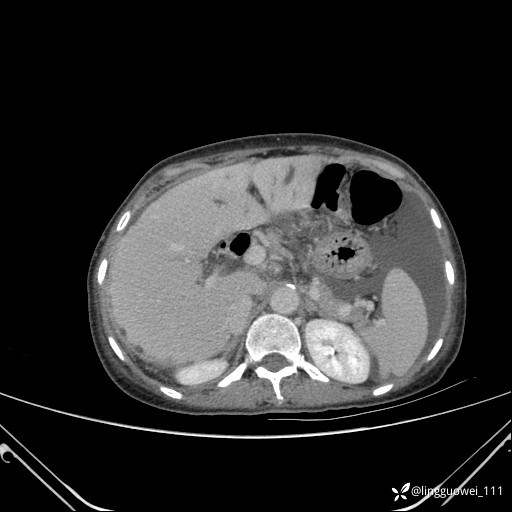

病例女,65岁,门诊行胃肠镜检查后,说腹胀入院检查,CT能发现病因吗?已公布结果

患者性别:女

患者年龄:65岁

主诉:门诊行胃肠镜检查后,诉腹胀,入院检查,肝有病变吗?腹膜及腹腔的表现有特征性吗?

门脉期: